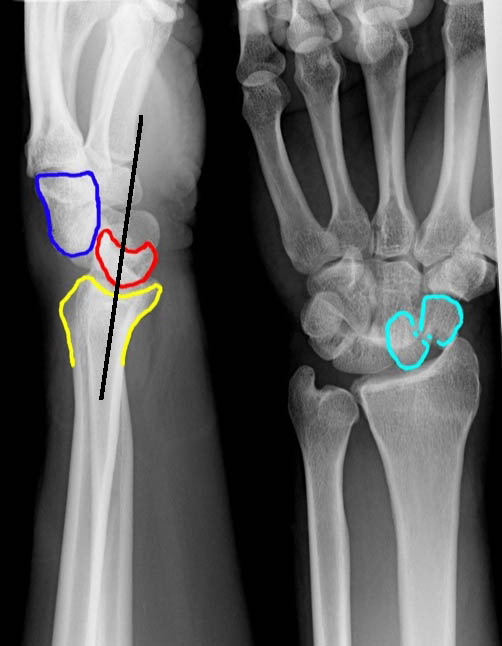

- Perilunate Dislocation

- Lateral view

- Capitate displaced dorsal to lunate

- Lunate retains its normal contact w/ radius

- PA view

- Capitolunate joint space is obliterated as the bones overlap one another